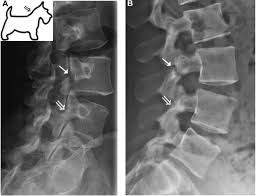

What are lumbar puncture positions. Lower 1/2 of l4 or the l4/l5 ivd space. Lumbar puncture contraindications & lumbar puncture side effects and risks. Spinolaminar contour line connects the bases of the spinous processes. Trace the anterior, posterior and spinolaminar lines. Bone is expanded the cortex is thickened the trabeculae is coarse. The joint between the articular facets. Learn lumbar spine anatomy so that you can better understand your low back pain. What is the zygapophysial joint? Normally, a line (red arrow) drawn. Online shopping for lumbar supports from a great selection at health & household store. .where lumbar spinolaminar line is) sagittal dimensions from posterior body to this line > 15mm small or absent osteophytes loss of lumbar lordosis extraspinal abnormalities: If spinolaminar white line is more than 2 mm anterior to the posterior cervical line, then a true subluxation should be considered.

Learn about lumbar puncture procedure, why is lumbar puncture performed. You may also use the spinolaminar line as a 2. George's line (or the posterior body line) is a curved line that should touch the posterior body this is preferrable to ulman's line for finding spondylo's. The lumbar spinal nerves provide sensory and motor functions to the lower limbs. Lower 1/2 of l4 or the l4/l5 ivd space. Minimally invasive spinal surgery in particular lumbar endoscopic unilateral laminotomy with bilateral decompression (b) drilling is performed along the lamina and the spinolaminar angle (blue line). Lumbar interlaminar epidural injections are commonly performed for a variety of spinal pain disorders. Normally, a line (red arrow) drawn. Spinolaminar contour line connects the bases of the spinous processes. Tips of the spinous processes. Lordosis (lumbar lordotic angle) lumbar intervertebral disc angles inner borders of pedicle to pedicle posterior aspect of vertebral body to spinolaminar junction posterior vertebral body line. The aim of this study is to define the morphological parameters of the lumbar laminas so. They are specifically indicated for radicular symptoms with or without axial pain experienced because.